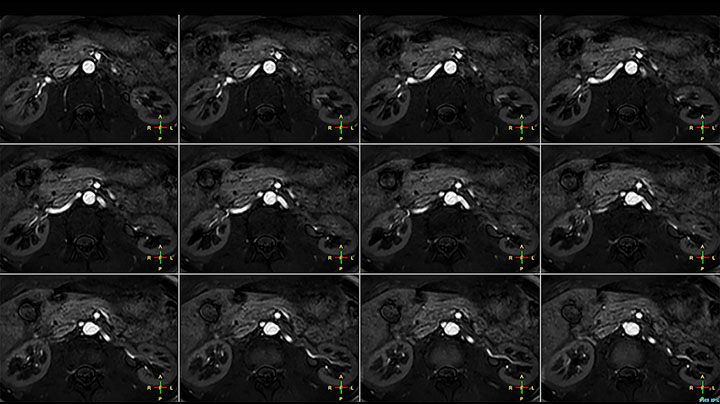

The Prodiva shoulder coil is very flexible and has large coverage, which makes good positioning easier, and that contributes to the superb image quality and high SNR that we get in our shoulder exams.

Scan time 2:55 min, FOV 160 mm, acq voxels 0.55 x 0.83 x 3.0 mm.

Scan time 4:19 min, FOV 160 mm, acq voxels 0.55 x 0.80 x 3.0 mm.

Scan time 2:50 min, FOV 160 mm, acq voxels 0.70 x 0.99 x 3.0 mm.